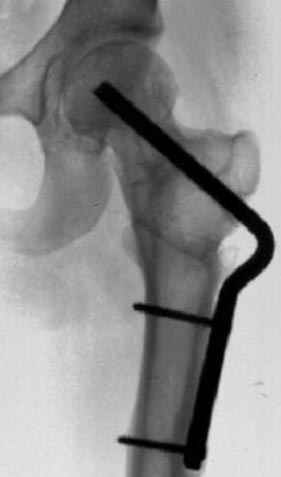

Отправитель: Alexander Chelnokov 23 Ноябрь 2004, 02:31

Если, например, доводится лечить больных с псевдартрозами шейки бедра, то надобность есть, и приходится. См. приложение.

Несколько снимков из моей коллекции, чтобы разьяснить, почему мы до сих пор делаем различные варианты остеотомии.

На рисунке N1 предоперационный план лечения ложного сустава шейки бедра- линия ложного сустава, угол и направление введения импланта, клиновидная остеотомия в градусах и миллиметрах, второй снимок после коррекции, расчет, на сколько удлиняется конечность и размеры импланта;

N3 рисунок окончательный снимок, после операции моя рентгенограмма должен выглядеть примерно как эта картина. На N4 снимке клин перед удалением; N5 послеоперации 3 нед.; N6 окончательная рентгенограмма.

(доложен в Ст. Петербурге 2003 и в Москве 2004)

варус при проксимальном отделе 95 градусной пластиной.